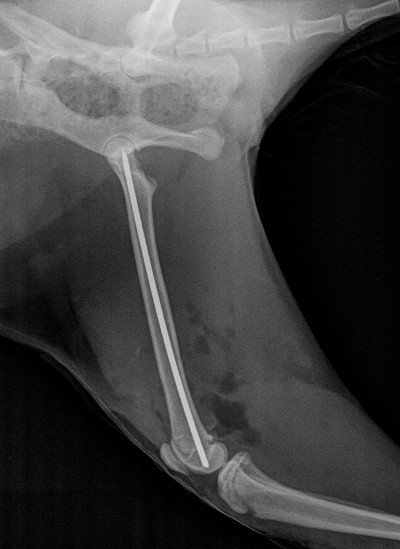

Figure 1